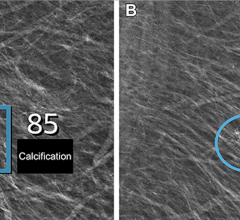

The study details the results of a comprehensive comparison of available mammographic density measurement tools and their ability to predict breast cancer risk. The performance of three area-based approaches (BI-RADS, the semi-automated Cumulus, and the fully-automated ImageJ-based approach) and three fully-automated volumetric methods (VolparaDensity from Volpara Solutions, Quantra from Hologic, and single X-ray absorptiometry (SXA)) were assessed in 3,168 digital mammography images. This included cancer cases diagnosed at Royal Marsden Hospital in London and normal mammograms from the England and Wales national mammographic screening program.

All six density assessment methods showed that percent density was inversely associated with age and body mass index (BMI), and certain reproductive factors. While all of the methods produced positive associations of density with risk, the association was highest for Volpara and Cumulus. Volpara and Cumulus were also the only tools that produced breast density measures for all images in the study, with other methods failing to produce readings for up to 11% of the participants. Women with the highest density had 8.26 times the risk of those with the lowest breast density as measured by Volpara on this dataset (the 95% confidence range was 4.28-15.96). The results also suggest that Volpara is better at identifying women at low risk than the other methods.

Cleared by the FDA, HealthCanada, the TGA and CE-marked, VolparaDensity is used by radiologists to objectively assess density from both digital mammography and tomosynthesis images to help doctors evaluate who might benefit from additional screening. Highly correlated to breast MR assessments, VolparaDensity is a reliable tool that automatically generates an objective measurement of volumetric breast density correlated to the ACR (American College of Radiology) breast density categories. To date, more than 3-million women have had their breast density analyzed, using VolparaDensity. VolparaDensity is part of a suite of quantitative breast imaging tools built on the Volpara Solutions algorithm that allows for personalized measurements of density, patient dose, breast compression and other factors designed to help maintain accuracy and consistent quality in breast screening.